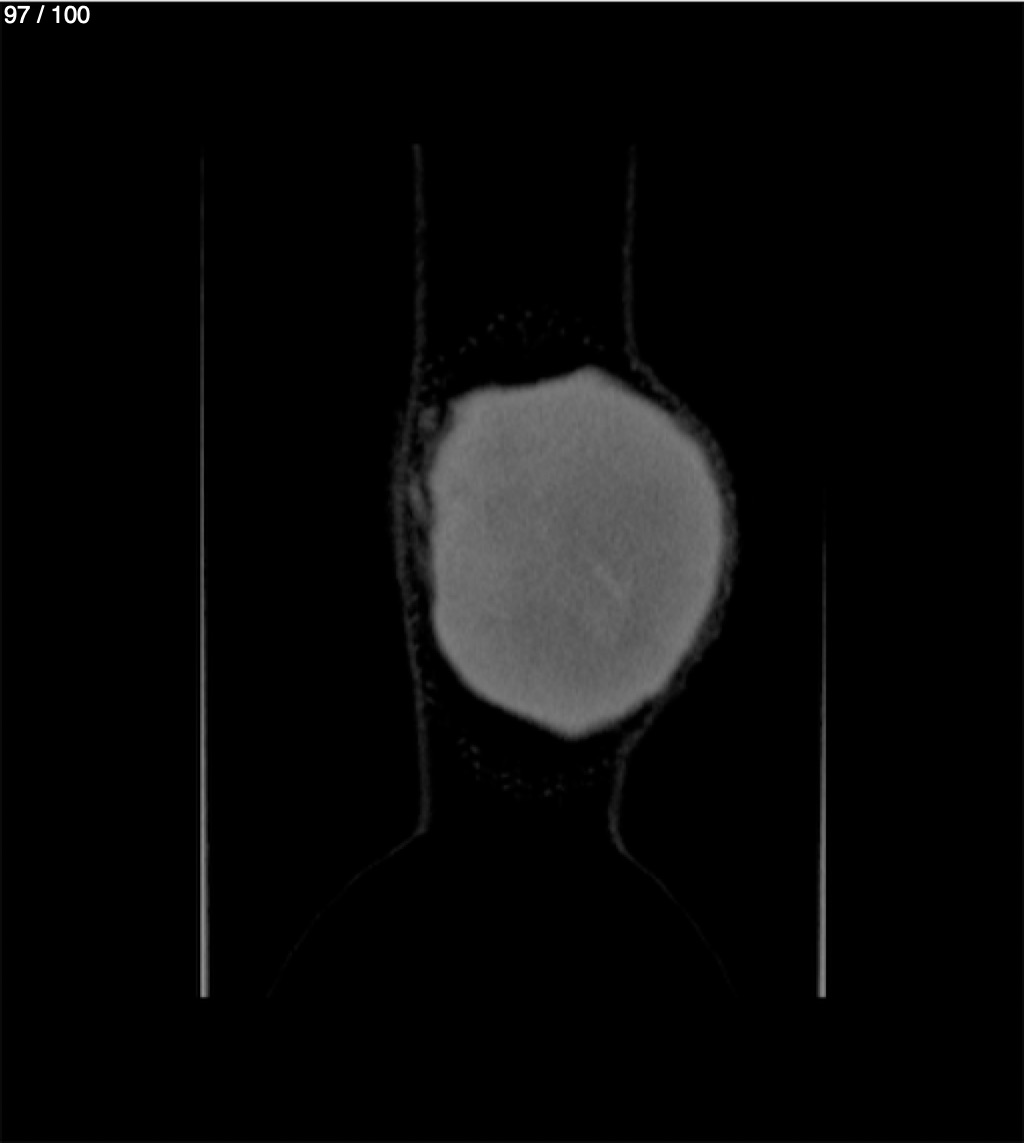

Yonelly Barrios Diaz 35A - T.C Craneo